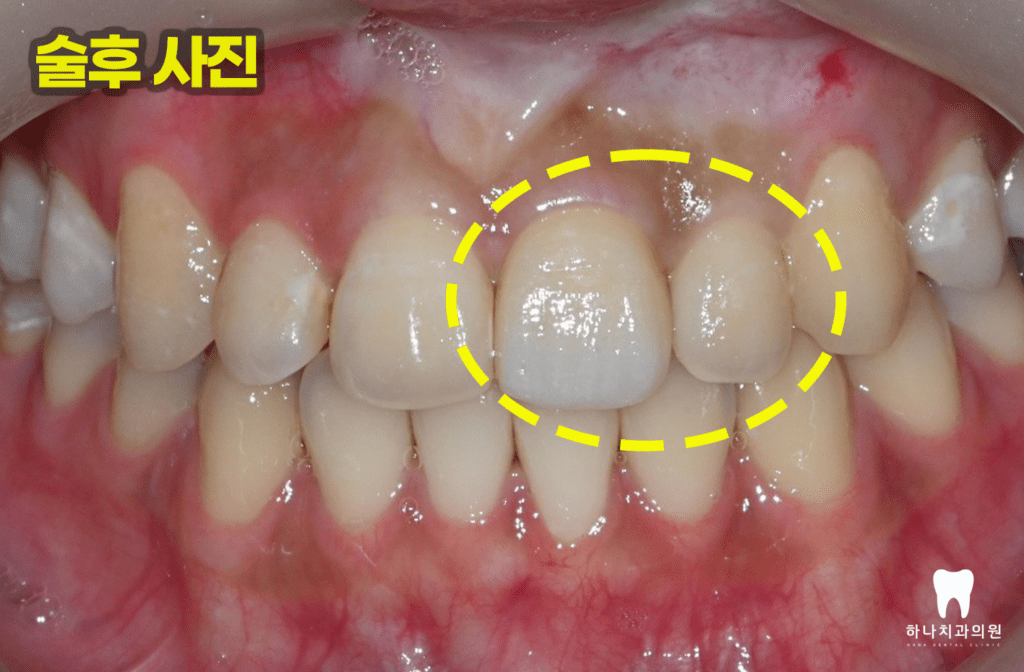

20대의 젊은 여성분이시지만

매우 어두운 색조를 가지고 계셨기 때문에

크라운의 양옆 자연치의 색깔에 맞춘다면

자연스러워 보이겠지만 심미적으로

좋지 않을 것을 우려해

크라운의 색조는 한 단계 밝게

디자인하고 미백 치료로

자연치의 밝음 정도를 조금 올리는

방향으로 계획을 하였습니다.

이유는, 치아 미백 시 자연치의 색조는

밝아질 수 있으나 보철물은 변화하지

않기 때문입니다.

크라운과 레진 수복까지

마친 모습입니다.

앞니 치료에서는 단순히 하얗고

가지런한 치아를 만드는 것보다

환자의 얼굴 형태와 입술 움직임,

치아 비율 등을 고려한 디자인이 필요합니다.

환자분께서도 “딱 좋아요~!

나중에 미백 치료를 해서

옆의 치아와 색깔을 맞추면

더 이쁠 것 같아요.”

라고 말씀하시며 아주아주

만족해하셨습니다.